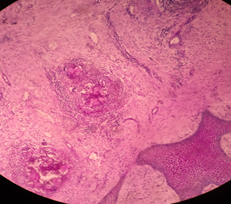

Histopathology is useful in confirming the clinical diagnosis and distinguishing eumycetomas from actinomycetomas, but it does not identify the causative agent. Histological sections reveal a granuloma containing grains located in the microabscesses (Figure 2).5 Grains can be visualized with hematoxylin-eosin (H&E) staining and by special staining techniques, such as periodic acid-Schiff (PAS) and Grocott stain. Actinomycetes can also be analyzed using the Gram technique. In eumycetoma, grains are characterized by clusters of radially branched hyphae that occasionally form vacuoles. Long, clear hyphae can be observed, surrounded by a basophilic component (H&E stain). The grains are round, sometimes oval or kidney-shaped (Figure 3).

Figure 2 Granulomas containing localized grains.

Figure 3 Actinomycetic granuloma.